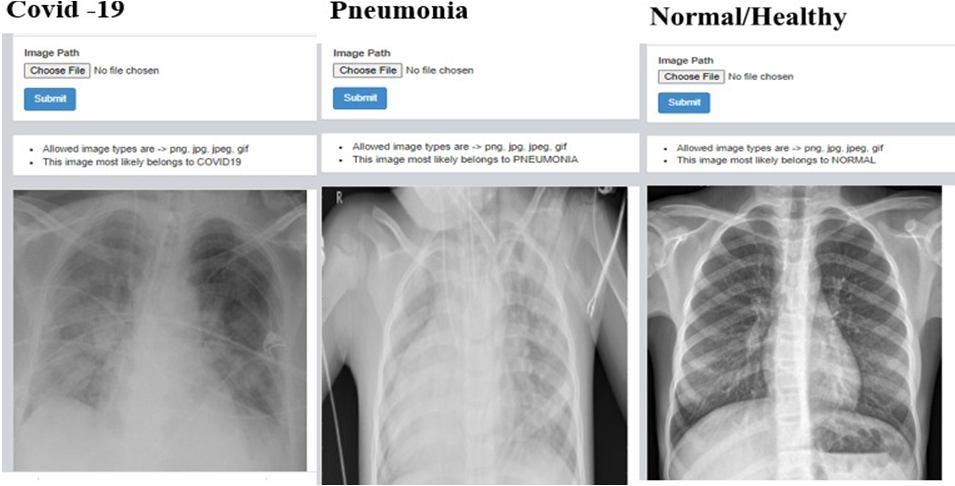

G. Results of web application

1) Detection of Covid 19 , Pnuemonia and Healthy chest x ray: Here the X ray images are fed by clicking on choose file in dash board after that we need to select file in which the images are present and upload it once after uploading needto click on submit button once after the submiting image we can observe result whether the given X ray belong to covidor pneumonia or normal.The same procedure is followed for many iteration to check whether develop web application is accurate by feeding different types of X ray images.

Fig. 18: Iteration 2 Fig. 19: Iteration 3 Fig. 20: Iteration 4

Fig. 21: Iteration 5

Fig. 22: Iteration 6